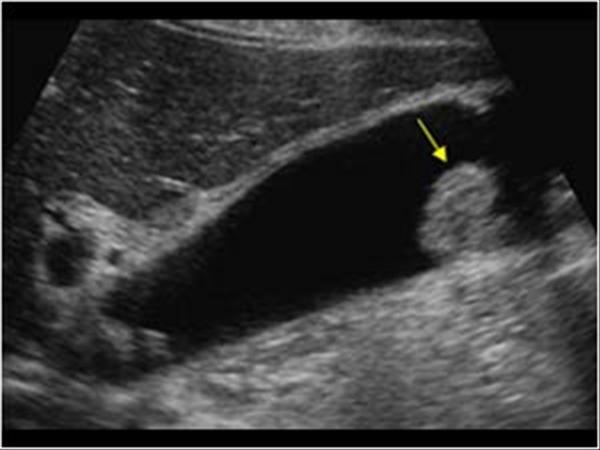

sludge balls are also called _________

tumefactive sludge

ultrasound appearance of sludge balls

avascular mass with low-level echoes